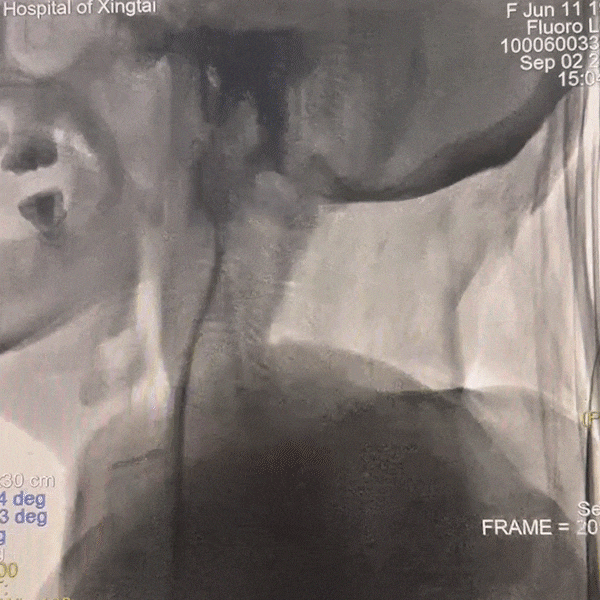

患者为右侧大脑中动脉狭窄,术前查右上肢血管彩超提示右侧桡动脉远端内径3.6mm、近端内径4.5mm,故选择经右侧远桡动脉入路进行手术。

通路建立:右侧远桡动脉置鞘成功,5F多功能导管尝试超选右侧颈总动脉失败。

撤出多功能导管和短鞘,交换088输送导管至右侧锁骨下动脉近端,沿输送导管送入赛诺神畅APEX TRA GC™5F-130cm SIM2至主动脉弓,成袢后轻松超选入右侧颈总动脉,同轴沿SIM2导管将输送导管送入右侧颈总动脉,撤出SIM2导管,沿导丝将6F 115cm远端通路导管送至右侧颈内动脉C4段。